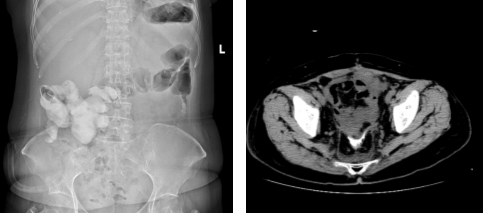

邓大姐于术后第三周如期开始了首次静脉化疗。术后第四周,影像学证实支架已完全降解,转流管成功拔除。

术后腹部平片可见小肠支架完全降解(左),肠道造影发现吻合口愈合良好(右)

“转流管拔掉之后,剩下一个香烟直径大小的小洞,慢慢愈合,越变越小,偶尔会有一些液体渗出,我自己也能根据护理团队教我的方法处理,很简单。”目前,邓大姐已经做完4次化疗,还剩下2次,“除了化疗那几天会有点没力气、胃口差点,其他方面跟没生病之前没什么差别。我自认为算是一个‘挑剔’的人,但手术至今3个月,没觉得有特别难受的地方。”相较于卵巢癌超根治术后预防性人工造口的患者营养状况差、体重丢失多的常见现象,邓大姐不仅没有消瘦,还重了三四斤。“术前111斤上下,现在115斤。”